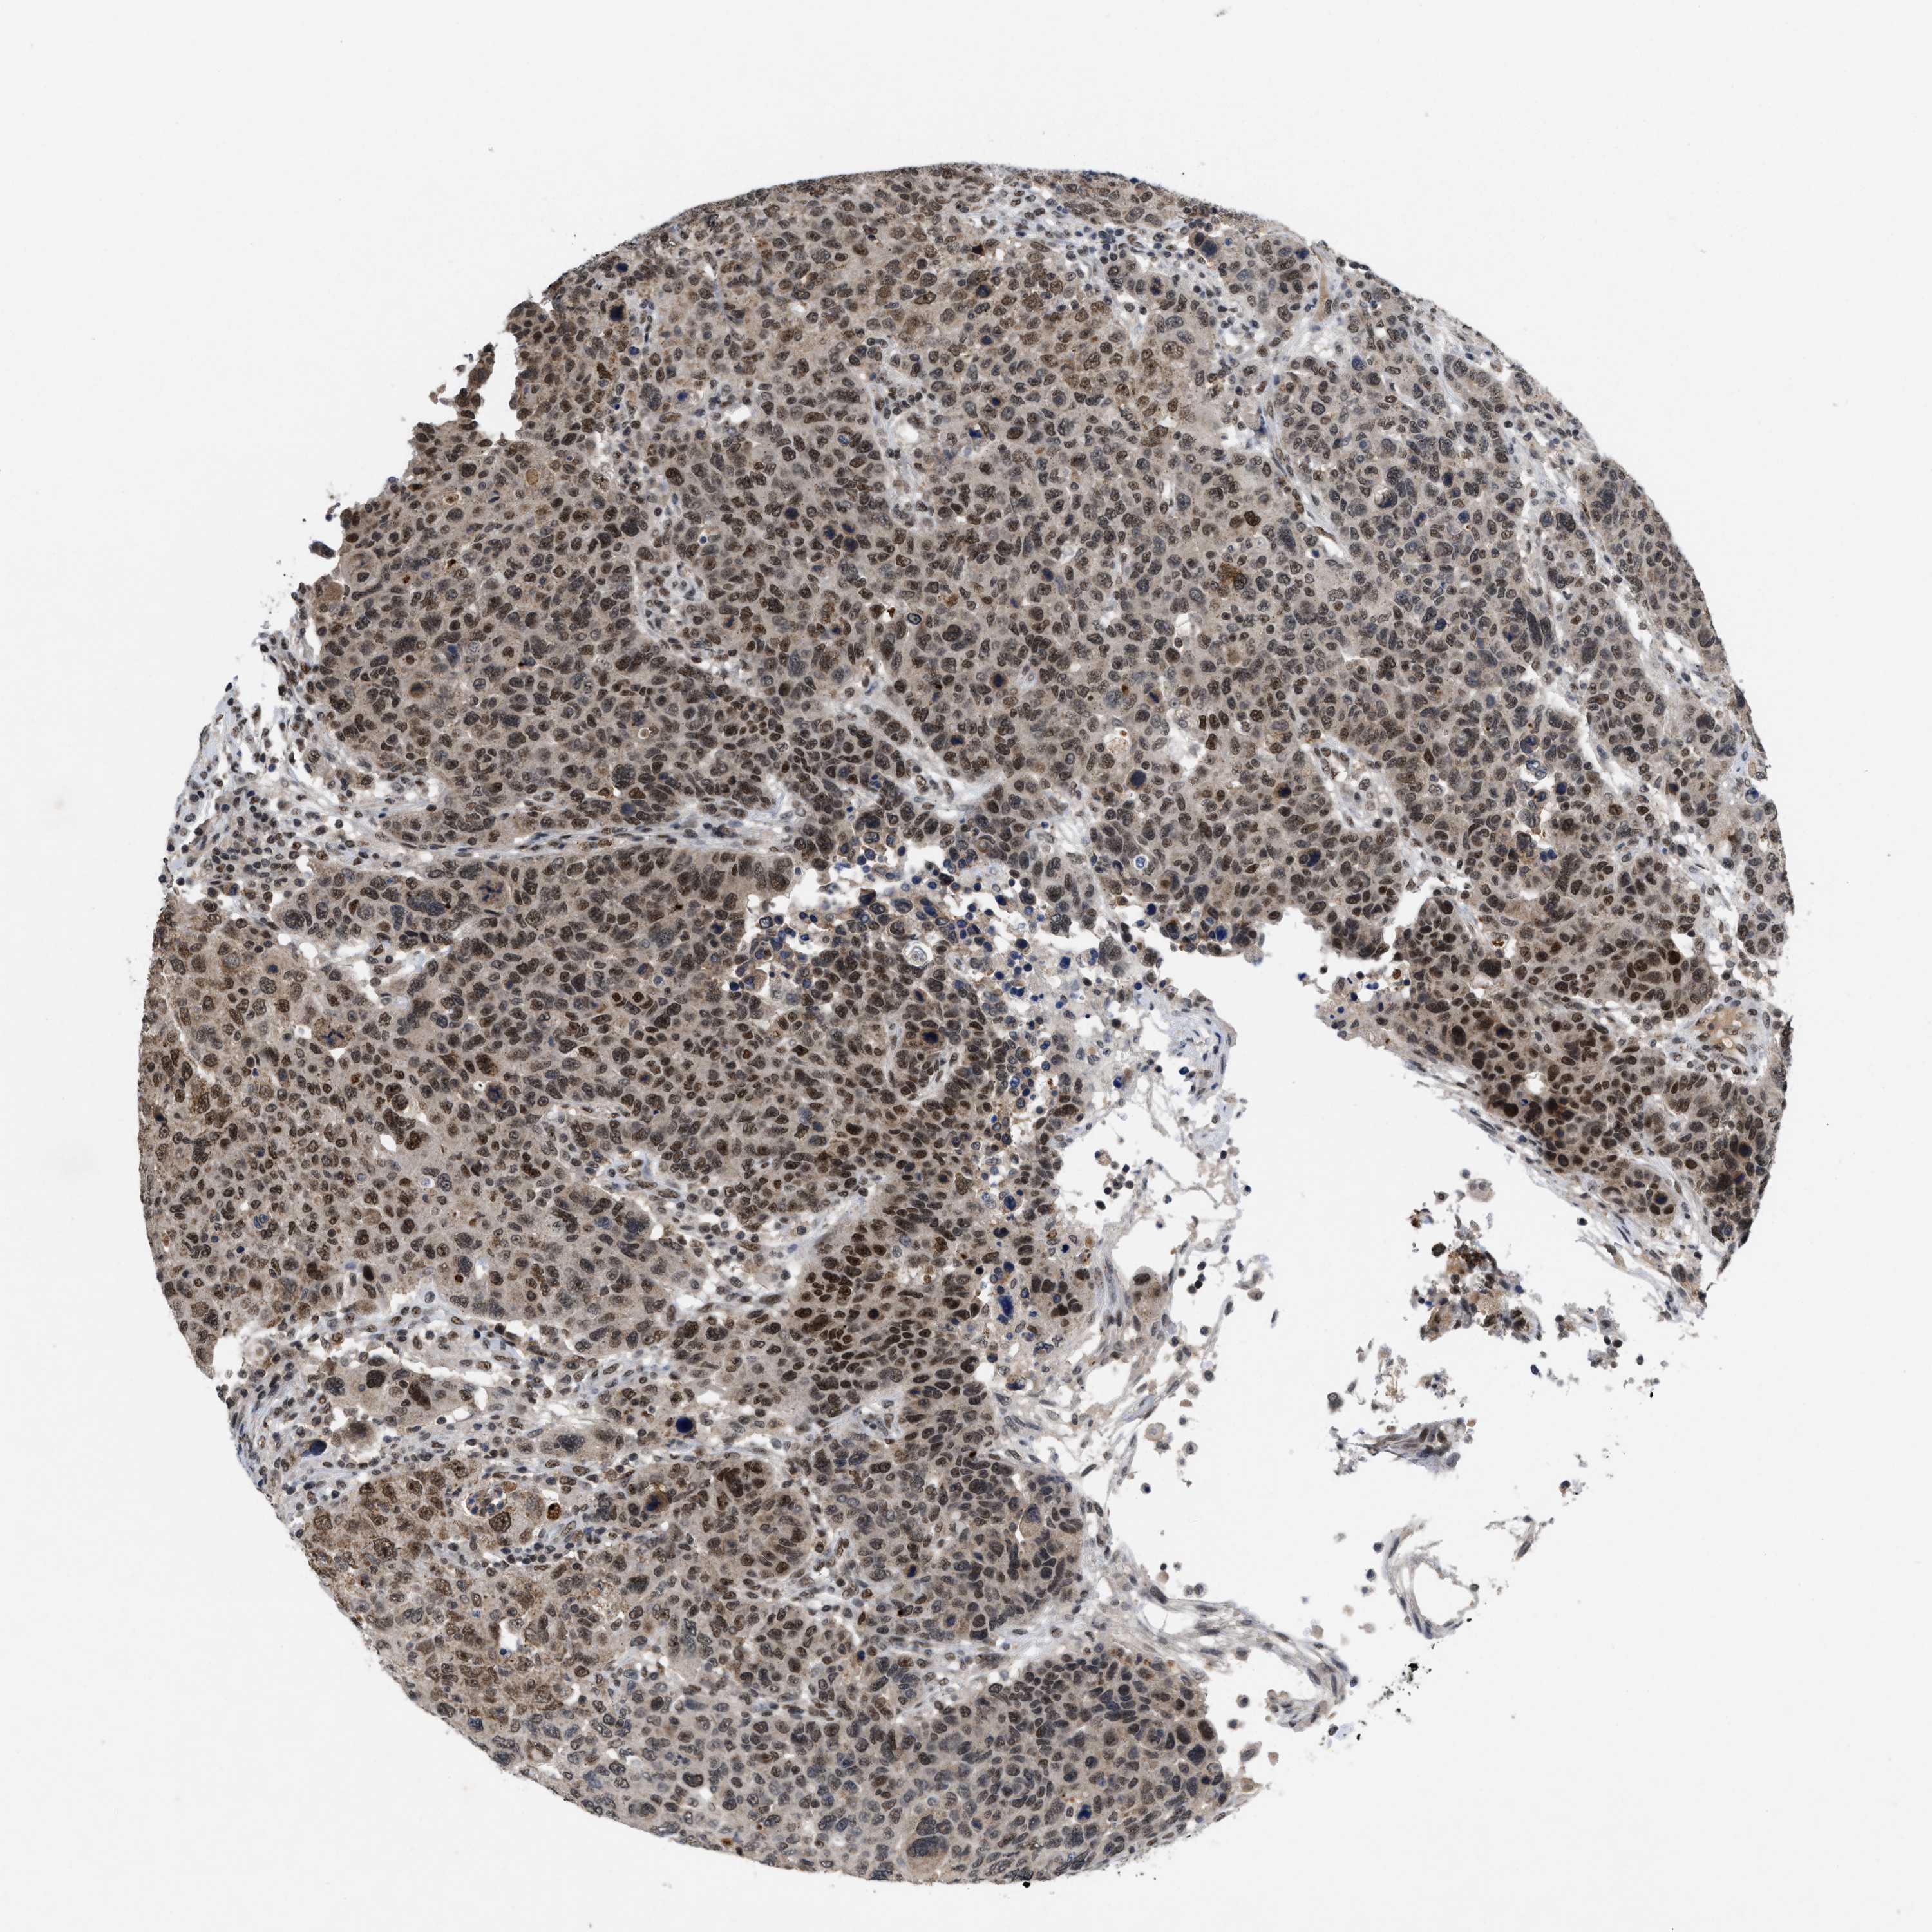

BRCA TCGA BRCA VALIDATION PROTEIN EXPRESSION